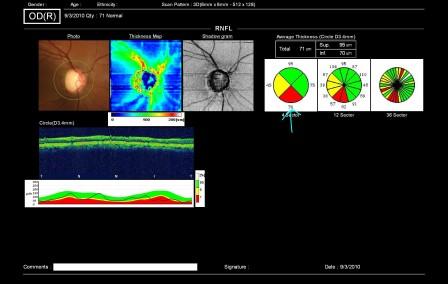

↑ これが実際の緑内障患者様の検査結果ですが、上の写真の水色の矢印部分、視神経の下側が減ってしまっているのが分かります。減ってしまっている部位は赤色、もしくは黄色で表示されます。